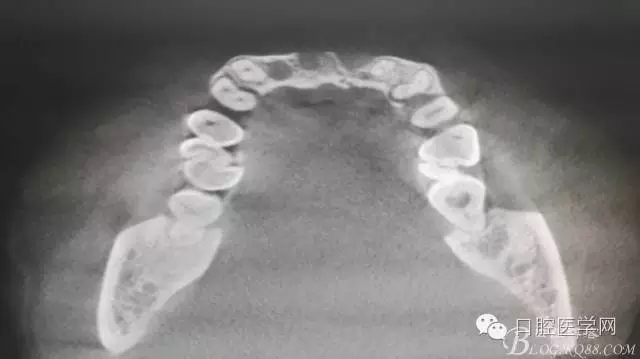

為他院轉(zhuǎn)診患者。男,無(wú)吸煙史,前牙因齲壞治療后,外力折斷導(dǎo)致拔除?,F(xiàn)拔除該牙后兩個(gè)多月。 左上區(qū)域骨寬度不足,計(jì)劃植入種植體同期GBR。

左上區(qū)域骨寬度不足,計(jì)劃植入種植體同期GBR。